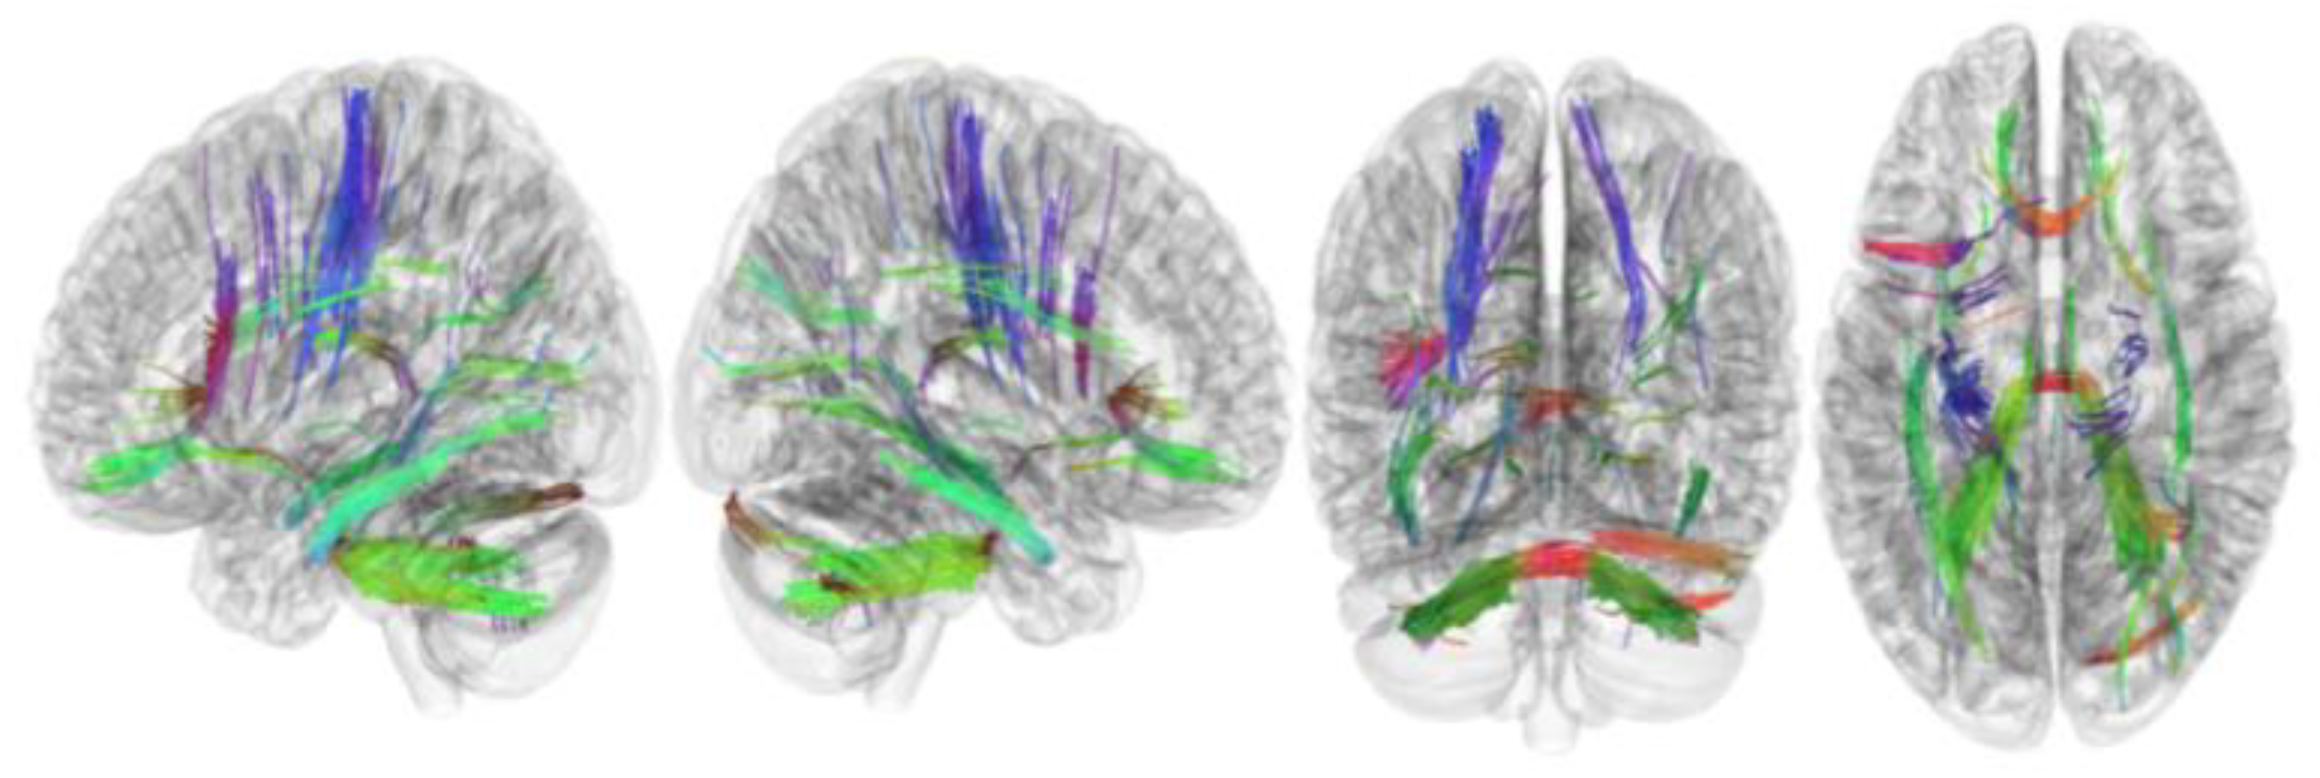

3.3. Tracks with QA Correlated with RLS Severity

| QA | |

| Tracks with positive or negative correlation with RLS severity | None |